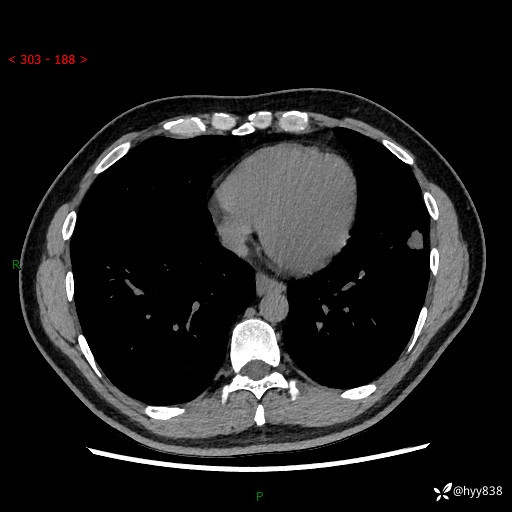

中年男性,胸闷3月余。多发团片、肺小叶分布、空气支气管征、明显强化---结果公布~

现病史:患者3月前出现胸闷,卧位时加重,坐位时缓解,无咽痛、咳嗽,无头痛,无全身酸痛,无结膜充血,无胸痛、心慌,无咯血,无呼吸困难,无咳痰,2024-07-02于当地市第一民医院行胸部CT,结果不详,2024-07-05就诊于我院急诊内科,行胸部CT同时增强,结果示:左肺下叶多发结节灶,考虑感染可能。今患者为求进一步诊治来我院,门诊以“肺部感染”收入我科。 患者本次起病来精神、食欲、睡眠尚可,大小便可,体力,体重无明显变化。

胸部CT平扫+增强

各期CT值:30hu 90hu 77hu